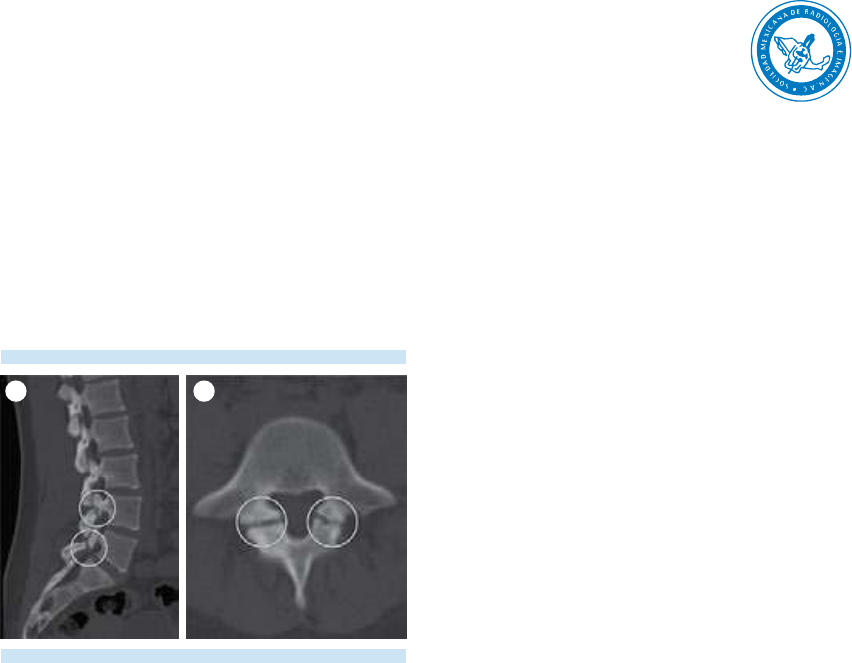

4. Evaluación de las articulaciones face-

tarias, láminas, pedículos, procesos

transversos y espinosos; del canal central

y los recesos laterales.